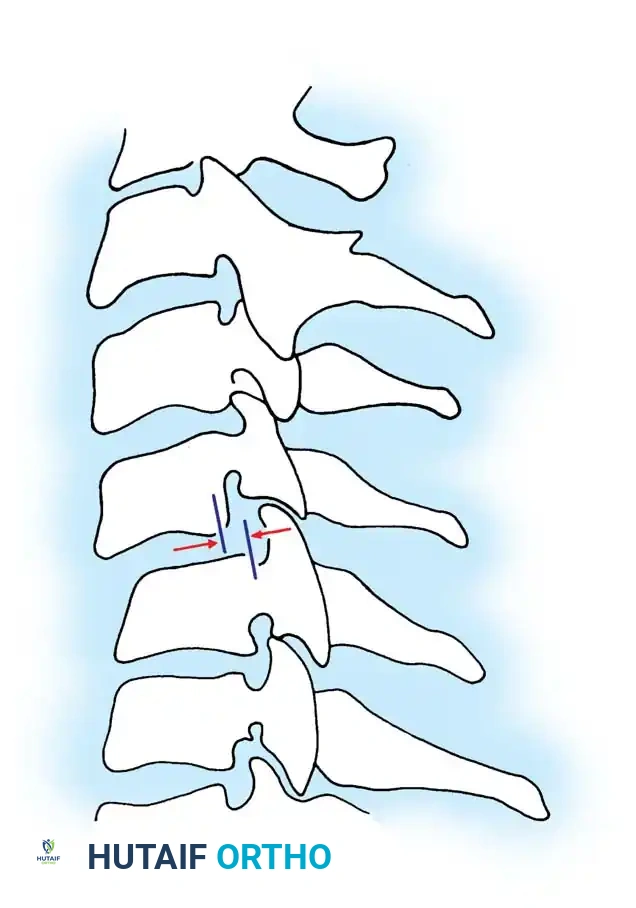

* Relative sagittal plane translation > 3.5 mm: 2 points

Fig 3. Sagittal plane translation of more than 3.5 mm suggests clinical instability.